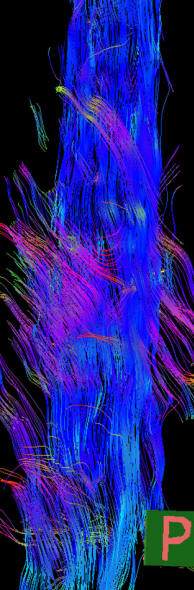

MRI of the dorsal spine with contrast and myelography and fibertraking and spectroscopy showing the recent lesions as seen in the below pictures with abscess formation.

MRI showing the new flare with abscess malformation and the old one

Fibertraking of the spinal cord at the lesion showing some scanty fibers ready for attack from behind (The middle picture)

Spectroscopy confirming the tbc abscess nature of the flare. High lipid and the choline is due to contamination of the voxel.